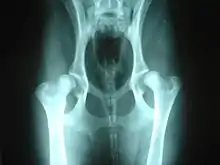

Hip dysplasia may be helped by hydrotherapy.

A number of conditions in dogs may be aggravated by or may show slow or no improvement as a result of weight bearing exercise. Among these are hip dysplasia and osteochondritis dissecans (OCD), conditions most common in medium to large purebred dogs, such as German Shepherds, Labrador Retrievers or Golden Retrievers; chronic degenerative radiculomyelopathy (CDRM), a degenerative disease of the spinal cord which causes hind limb problems in German Shepherds; and luxating patella which is seen predominantly in small and toy breeds.[2]